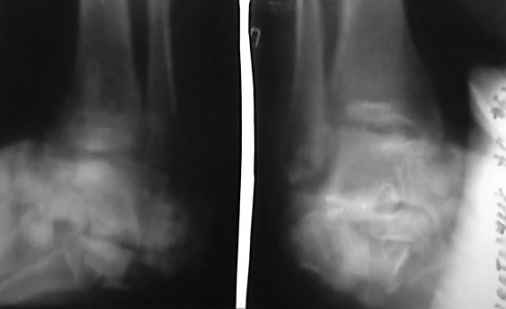

Отправляю снимки(свежие)и фото стоп.

С уважениемД.Б.

Жуткая картинка!

Мне кажется, что сейчас это больной для отделения гнойной хирургии. Выставляете ли Вы диагноз остеомиелит? Слева вполне может закончится ампутацией, а протезирование даст лучший функциональный результат.

Смотрю фото ! Вот теперь все стало на свои места- не до синтезов и детралексов

Согласен с Алексеем, ампутация это выход и для хирурга и больного и с функциональных и экономических соображений.